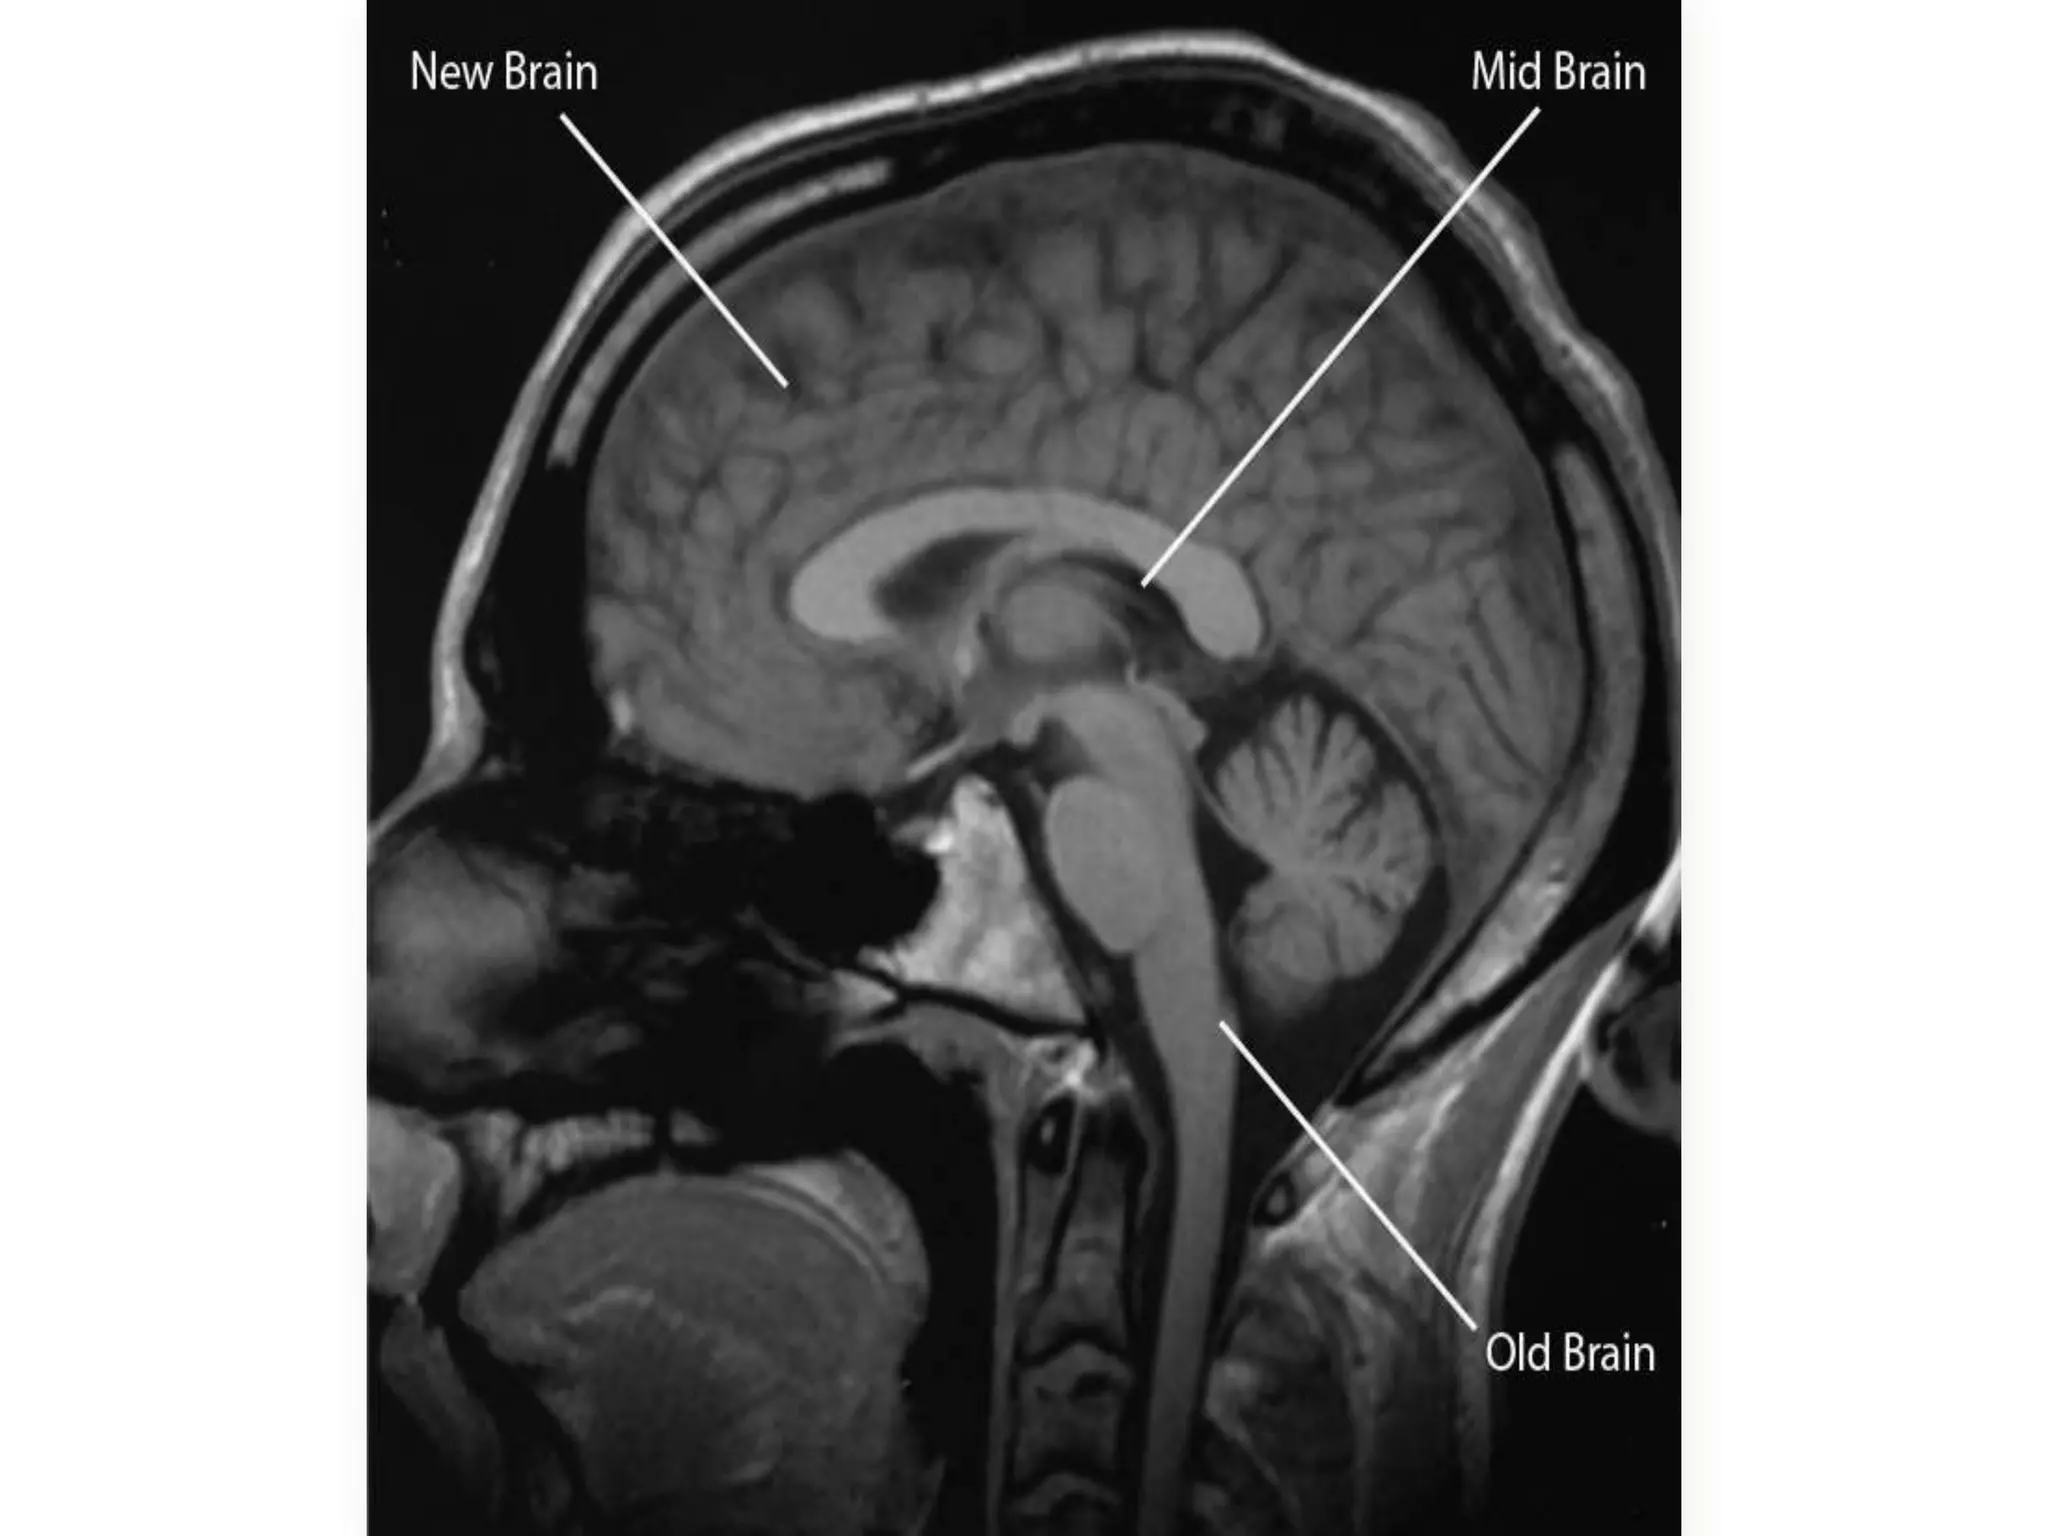

unconscious